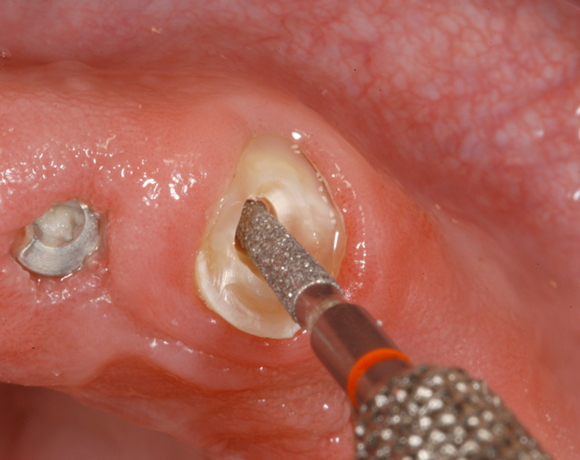

Im nachfolgenden Patientenfall wird ein Zahn mit einem Stift soweit aufgebaut, dass es möglich wird ihn wieder mit einer Krone zu versorgen.